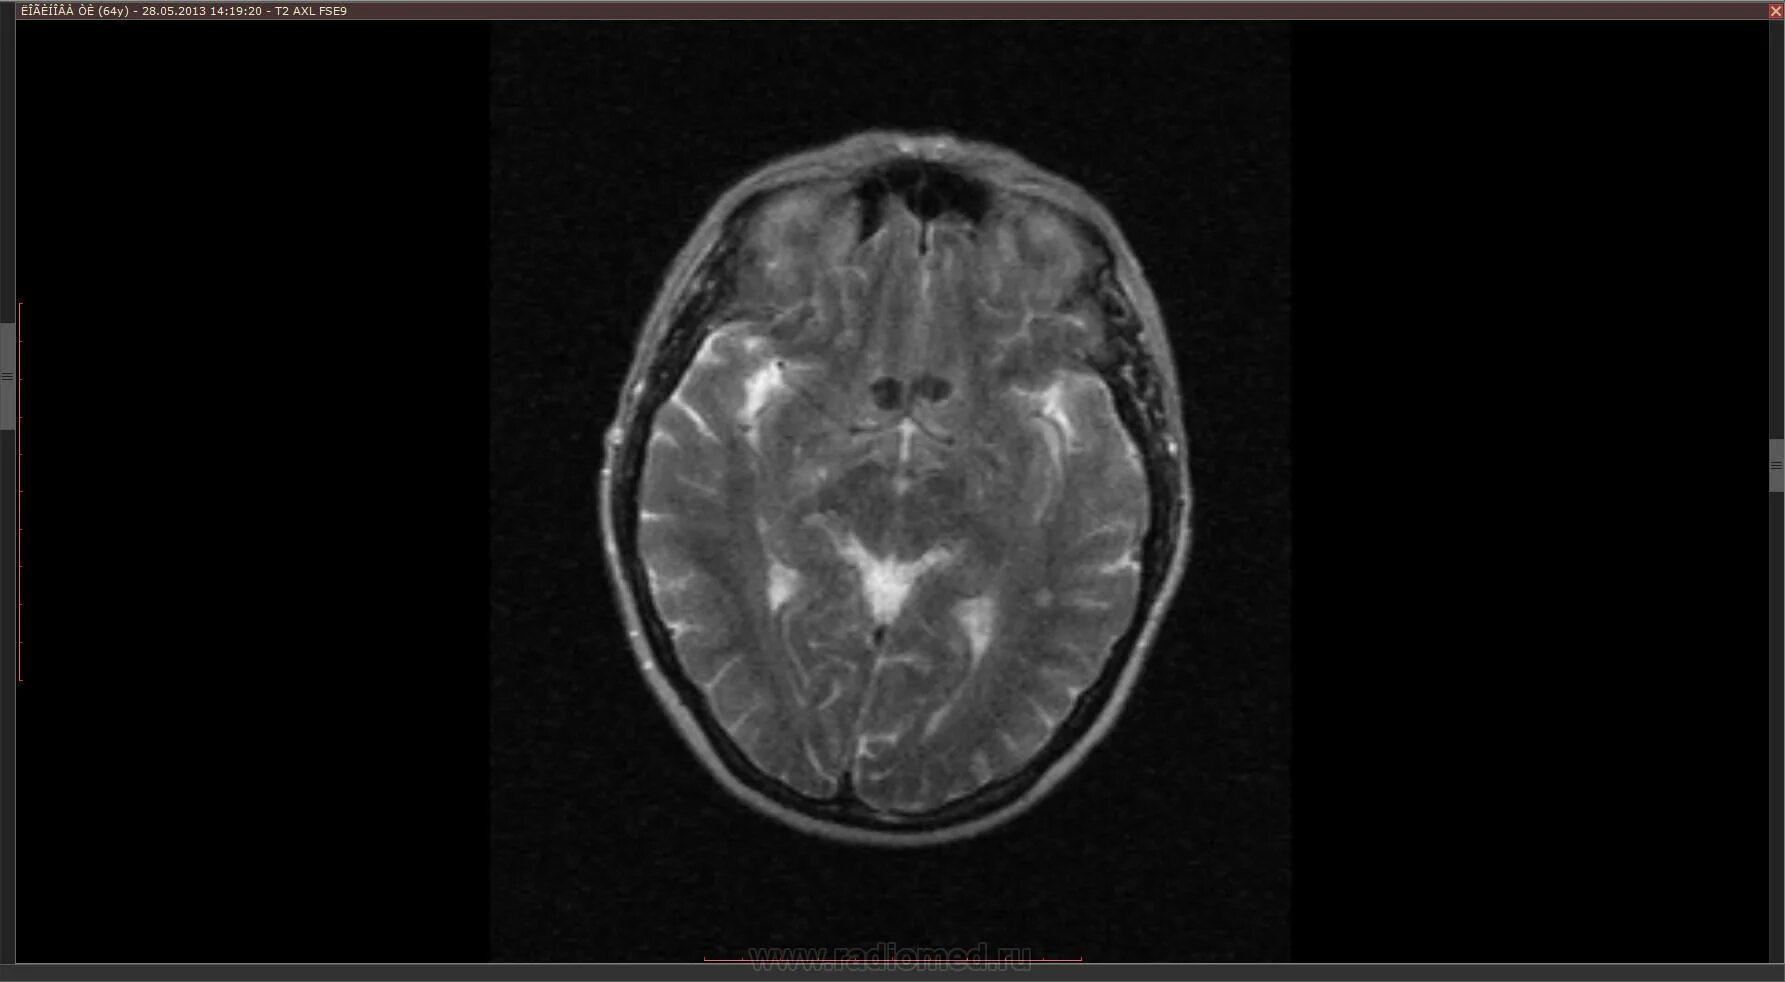

Мрт головного мозга и сосудов тула